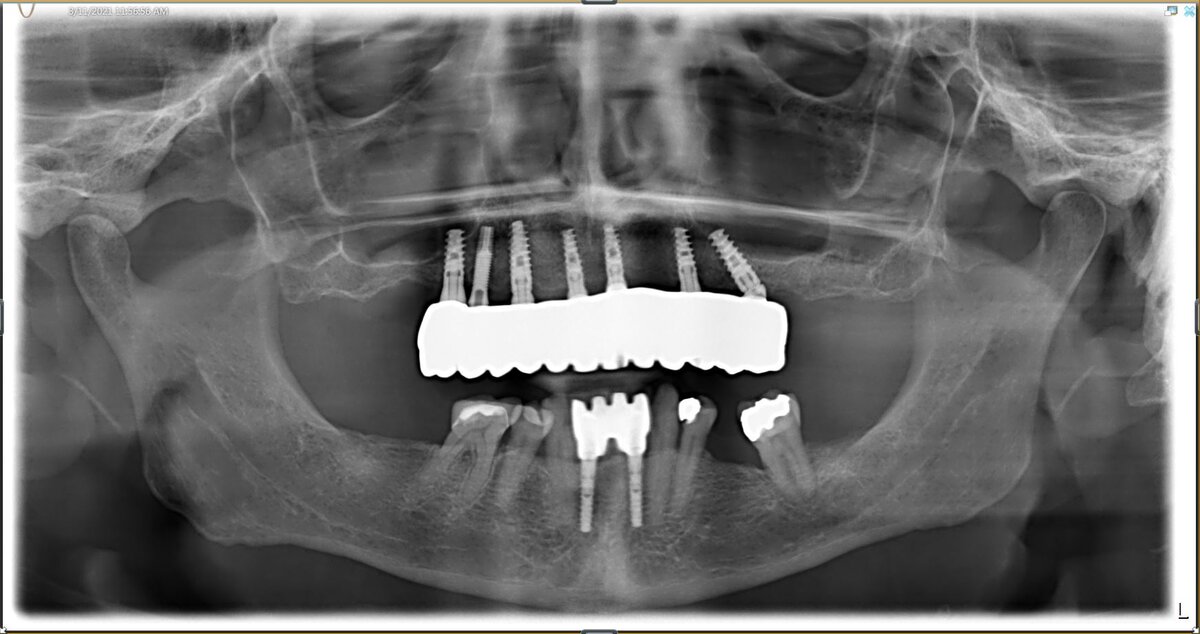

КЕЙС: All-on-six с немедленной загрузкой гибридного моста на имплантатах Adin

ИСХОДНАЯ СИТУАЦИЯ: мужчина, 55 лет.

В анамнезе имеется гипертоническая болезнь. В ротовой полости наблюдается дефект переднего мостовидного протеза, тяжелое кариозное поражение опорного зуба № 11 и генерализованный хронический пародонтит на оставшихся зубах. Кроме того, ранее был установлен имплантат в области зуба № 4.

В ходе операции были удалены верхние оставшиеся зубы, а также установлены и зафиксированы 6 имплантатов Touareg CloseFit менее чем за 24 часа, что позволило избежать отсутствия жевательной функции и психологической травмы благодаря быстрой реабилитации. После завершения хирургического этапа и успешного завершения процесса остеоинтеграции имплантата были сняты оттиски для окончательной реабилитации в монолитном диоксиде циркония с фарфоровым слоем.